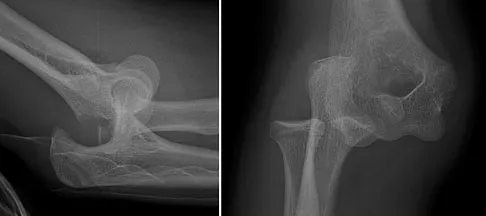

A 13-year-old gymnast has had recurrent right elbow pain for the past year. She denies any history of trauma. Rest and anti-inflammatory drugs have failed to provide relief. Examination reveals no localized tenderness and only slight loss of both flexion and extension (10 degrees). What is the most likely diagnosis?

Explanation

Osteochondritis of the capitellum is characterized by pain, swelling, and limited motion. Catching, clicking, and giving way also can occur. It commonly affects athletes who participate in competitive sports with high stresses, such as pitching or gymnastics. Krijnen MR, Lim L, Willems WJ: Arthoscopic treatment of osteochondritis dissecans of the capitellum: Report of 5 female athletes. Arthroscopy 2003;19:210-214.